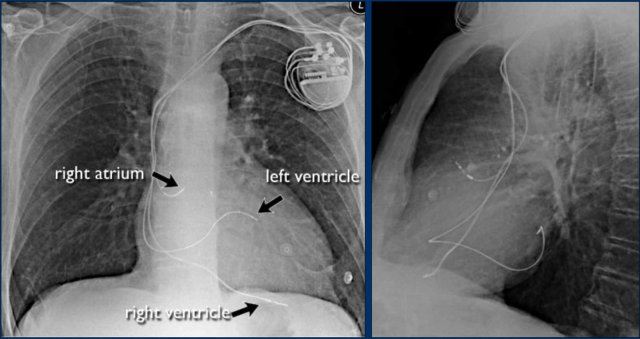

Cardiac Pacemakers

There are various types of cardiac pacing devices, each with specific lead configurations.

In this example:

• Right atrial lead

• Right ventricular lead

• Left ventricular lead via the coronary sinus (used in cardiac resynchronization therapy)

Indication for cardiac resynchronization therapy:

• Patients with ventricular dyssynchrony benefit from biventricular pacing, which improves ventricular coordination and enhances cardiac output.